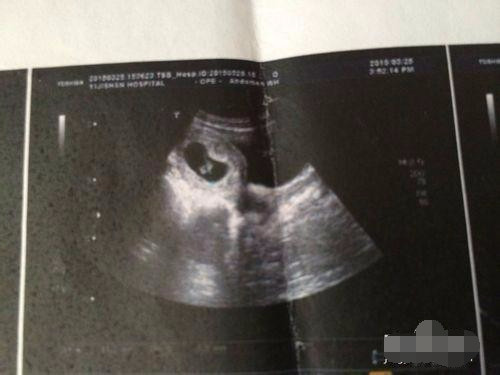

就这样喝了一个星期豆浆。怀孕52天去医院检查孕酮和HCG,测得孕酮就10了,反而降了。我很懊悔没有吃药。我超级担忧。HCG翻了一倍140000多。医生看后直接开了B超单,做过B超在看下一步。B超做的超级慌张。由于惧怕孕酮低招致宝宝发育不好或中止发育。结果出来后宝宝时分正常大小。医生便给我开了两个星期的黄体酮针。打针比拟快。并且下个星期继续复查。